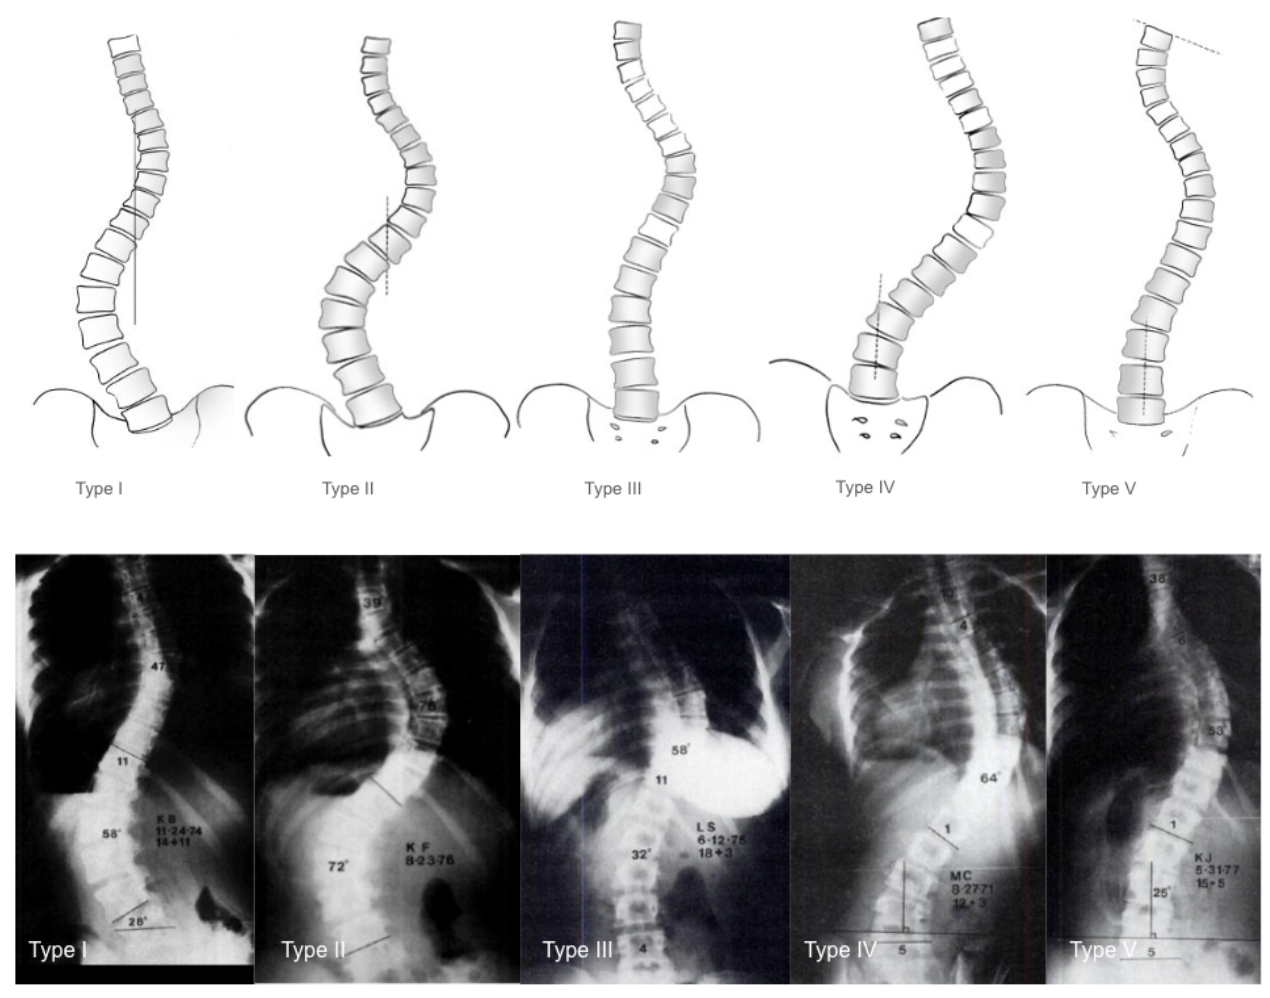

The system describes five coronal curve types (Types I–V), focusing exclusively on coronal alignment (based on the central sacral vertical line) without considering sagittal profile or three-dimensional deformity.

• Type I: S-shaped (double curve) with both lumbar and thoracic curves crossing midline; lumbar curve generally larger and stiffer than thoracic curve; FI is generally negative (thoracic curve ≥ lumbar curve standing and more flexible with side-bending)

• Type II: S-shaped (double curve) with both lumbar and thoracic curves crossing midline; thoracic curve generally larger and stiffer than lumbar curve; FI generally positive

• Type III: Prominent thoracic curve with minimal lumbar compensation (does not cross midline); thoracic ‘overhang’

• Type IV: Long thoracic curve where L5 is positioned over sacrum but L4 tilts into thoracic curve

• Type V: Double thoracic curve with T1 tilting into apex of upper curve; upper curve appears structural on side-bending